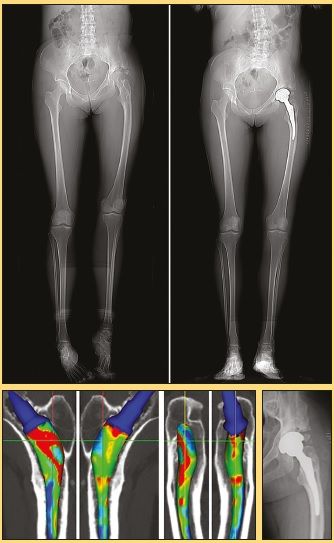

Step 1: The frontal and side on scout view can be used to perform length measurements outside and within the joint (Fig. 2).

1/ Intra- and extra-articular length

A frontal pelvic x-ray is generally used to achieve equal length. The most reliable technique is to use the line going through the ischiums (12), then to evaluate the position of the lesser trochanters with respect to the ischiatic line. This is easy to measure on an even pelvis but is more uncertain on a tilted pelvis, and inaccurate according to the study by HEAVER (12).

Also, it does not evaluate extra-articular length asymmetry. Unevenness is however common.

Patients are sometimes aware of it (history of fracture, etc.) but most often are not.

Hip arthroplasty aims to correct the intra-articular sector but it is useful to also be aware of extra-articular abnormalities. It is not uncommon to find the leg on the side affected by osteoarthritis of the hip to be up to one centimetre longer

The slightest prosthetic lengthening is likely to be very badly tolerated by the patient. We can do a hip-knee-ankle film, but this increases irradiation, or we can use an additional EOS.

The CT-scan scout view can be used to measure lower limb joint, segment and total length without additional irradiation and to determine the corrections to be made for the implant to the nearest millimetre.